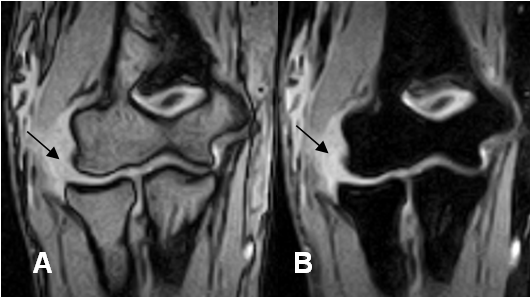

Fig 45 B. Ruptura del LCL.

A: RM coronal en GE y B: RM coronal en STIR. Presencia de líquido y solución de continuidad del LCL, por ruptura completa.